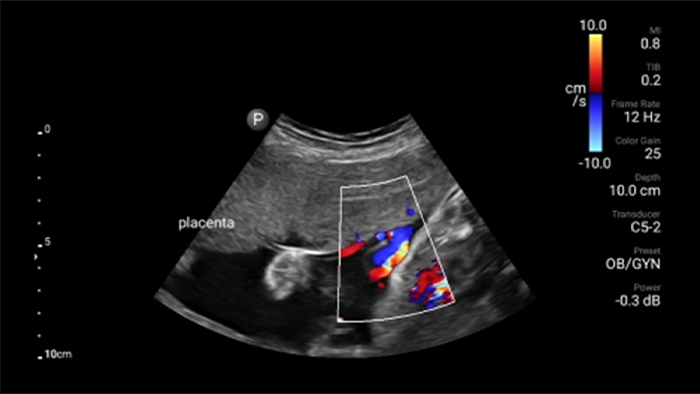

Lumify is with you every step of the way

Evaluate, diagnose and treat your patients in minutes with a multi-point POCUS exam.

See for yourself Get the full picture with clear whole-body imagery for a fast, accurate response during an emergency.

• 4 to 1 MHz extended operating frequency range • 2D, color Doppler, M-mode, advanced XRES and multivariate harmonic imaging • High-resolution imaging for abdominal and cardiac applications: Cardiac, OB/GYN, Lung, Abdomen and FAST imaging preset optimizations Lumify aids life-saving technology in prehospital setting

Focused Assessment with Sonography in Trauma (FAST) exam